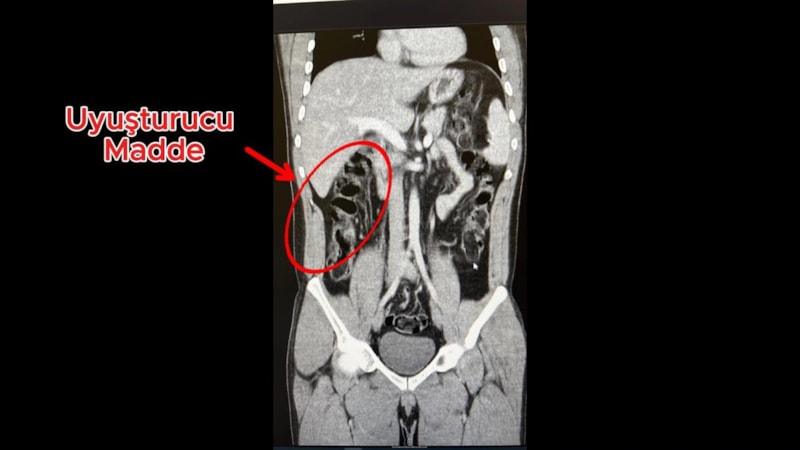

Hastanedeki iç beden muayenesinde, 2 şüphelinin, toplam 278 gram 35 kapsül halinde eroini yuttuğu saptandı.

Şüphelilerin havalimanındaki görüntüleri, muayene edilme anları ve yuttukları kapsüllerin yer aldığı film sonuçları, kameralara yansıdı.